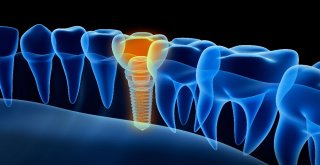

Saç Ekim Merkezi Direktörü Gülgör: Saçlarda Azalma Varsa Sebebi Azalan Testosteron Seviyesi Olabilir

Saç Ekim Merkezi Direktörü Gülgör: Saçlarda Azalma Varsa Sebebi Azalan Testosteron Seviyesi Olabilir